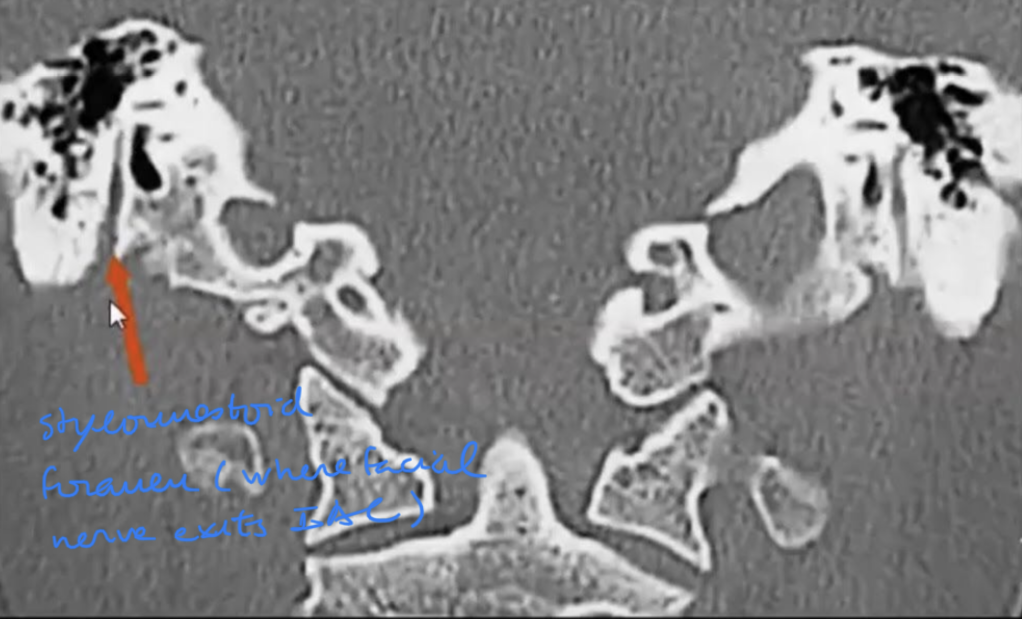

Tell the traject of the facial nerve in the skull base?

Nerves inside the IAC with subdivisions?